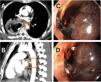

Unfortunately, 17 days after surgery, on Eid day (a national holiday), the patient arrived at the emergency room, having presented with 6–8 episodes of hematemesis. The patient was resuscitated with blood products, tranexamic acid, and vitamin K. His hemoglobin dropped from 7.7 to 5.6 over the next 20 h. A CT scan found an aneurysm at the T6 level on the anterior aspect of the aorta, measuring 10 × 7 mm, with a fistulous connection to the anastomotic site (Fig. 1A–C). There was no pleural leakage and no communication with the thoracic cavity. Endoscopy revealed a large adherent clot and fresh blood at the anastomosis site. Endoscopic attempts to close the fistula with endoclips (Fig. 1D) were unsuccessful. Urgent aortic stenting was performed, and follow-up CT angiography showed that the stent (length 2.9 cm) partially covered the fistulous communication (Fig. 2A and B). Re-stenting with a 4.6 cm stent completely covered the fistula (Fig. 2C and D). The patient was extubated and a nasojejunal tube was inserted. He was discharged on day 10, with long-term oral antibiotics. The patient’s post-operative rehabilitative state is good, and he is undergoing regular surveillance.

(A) Axial and (B) sagittal views of the CT aortogram after the first stent placement in the aorta, showing partial covering of the fistulous communication. (C) Axial and (D) sagittal views of the CT aortogram after the second stent placement in the aorta, showing complete covering of the fistulous communication.